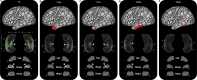

The hippocampus supports multiple cognitive functions including episodic memory. Recent work has highlighted functional differences along the anterior-posterior axis of the human hippocampus, but the neuroanatomical underpinnings of these differences remain unclear. We leveraged track-density imaging to systematically examine anatomical connectivity between the cortical mantle and the anterior-posterior axis of thein vivo human hippocampus. We first identified the most highly connected cortical areas and detailed the degree to which they preferentially connect along the anterior-posterior axis of the hippocampus. Then, using a tractography pipeline specifically tailored to measure the location and density of streamline endpoints within the hippocampus, we characterised where these cortical areas preferentially connect within the hippocampus. Our results provide new and detailed insights into how specific regions along the anterior-posterior axis of the hippocampus are associated with different cortical inputs/outputs and provide evidence that both gradients and circumscribed areas of dense extrinsic anatomical connectivity exist within the human hippocampus. These findings inform conceptual debates in the field and emphasise the importance of considering the hippocampus as a heterogeneous structure. Overall, our results represent a major advance in our ability to map the anatomical connectivity of the human hippocampusin vivo and inform our understanding of the neural architecture of hippocampal-dependent memory systems in the human brain.

The brain allows us to perceive and interact with our environment and to create and recall memories about our day-to-day lives. A sea-horse shaped structure in the brain, called the hippocampus, is critical for translating our perceptions into memories, and it does so in coordination with other brain regions. For example, different regions of the cerebral cortex (the outer layer of the brain) support different aspects of cognition, and pathways of information flow between the cerebral cortex and hippocampus underpin the healthy functioning of memory. Decades of research conducted into the brains of non-human primates show that specific regions of the cerebral cortex anatomically connect with different parts of the hippocampus to support this information flow. These insights form the foundation for existing theoretical models of how networks of neurons in the hippocampus and the cerebral cortex are connected. However, the human cerebral cortex has greatly expanded during our evolution, meaning that patterns of connectivity in the human brain may diverge from those in the brains of non-human primates. Deciphering human brain circuits in greater detail is crucial if we are to gain a better understanding of the structure and operation of the healthy human brain. However, obtaining comprehensive maps of anatomical connections between the hippocampus and cerebral cortex has been hampered by technical limitations. For example, magnetic resonance imaging (MRI), an approach that can be used to study the living human brain, suffers from insufficient image resolution. To overcome these issues, Dalton et al. used an imaging technique called diffusion weighted imaging which is used to study white matter pathways in the brain. They developed a tailored approach to create high-resolution maps showing how the hippocampus anatomically connects with the cerebral cortex in the healthy human brain. Dalton et al. produced detailed maps illustrating which areas of the cerebral cortex have high anatomical connectivity with the hippocampus and how different parts of the hippocampus preferentially connect to different neural circuits in the cortex. For example, the experiments demonstrate that highly connected areas in a cortical region called the temporal cortex connect to very specific, circumscribed regions within the hippocampus. These findings suggest that the hippocampus may consist of different neural circuits, each preferentially linked to defined areas of the cortex which are, in turn, associated with specific aspects of cognition. These observations further our knowledge of hippocampal-dependant memory circuits in the human brain and provide a foundation for the study of memory decline in aging and neurodegenerative diseases.